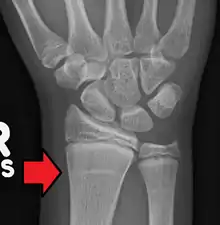

Growth arrest lines in a child with an underlying bone disease

Growth arrest lines, also known as Harris lines, are lines of increased bone density that represent the position of the growth plate at the time of insult to the organism and formed on long bones due to growth arrest. They are only visible by radiograph or in cross-section. The age at which the lines were formed can be estimated from a radiograph. Harris lines are often discussed as a result of juvenile malnutrition, disease or trauma. Other studies suggest a reconsideration of Harris lines as more of a result of normal growth and growth spurts, rather than a pure outcome of nutritional or pathologic stress.[1] The lines are named after Henry Albert Harris, 1886-1968, professor of anatomy at the University of Cambridge.[2]